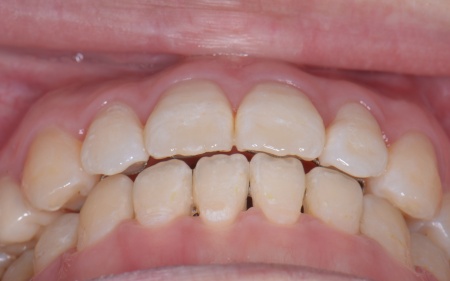

| カウンセリング | 拝見したところ、右上と左下の奥歯に強い痛みが出ていました。 レントゲンで確認した結果、どちらも歯の根が割れていることが判明しました。 歯の根が割れたまま放置すると噛むときの痛みが続くだけでなく、炎症が広がって周囲の歯や骨にまで影響を及ぼすおそれがあります。 また、上下の歯を噛み合わせた際に前歯が噛み合わず隙間ができる開咬(かいこう)と呼ばれる噛み合わせも見られました。 以上のことから、抜歯後に歯を補う治療と噛み合わせを改善するための治療が必要と診断しました。 |

患者様は「健康な歯をできるだけ守りたい」との理由から、③のインプラント治療を希望されました。 まず、右上と左下の奥歯を抜歯しました。 矯正がある程度進んだ段階で、右上と左下のインプラント手術を実施しました。 インプラント手術後は矯正治療の仕上げを行い、装置を外しています。 治療終了後、下前歯の間に見られる三角形のすき間(ブラックトライアングル)が気になるとのご相談がありました。 |